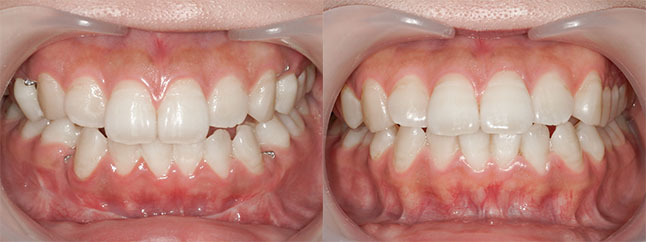

奈良県 20歳 女性

執刀医 辻和志

【治療内容】上下のアゴが前に出ていたため、上下のアゴの骨を切って後ろにさげました。

【費用】上下セットバック 2,307,800円(税込)

【リスク】全身麻酔で行うため全身の健康状態が悪い方は行うことができません。また、手術当日は安静にしていただく必要があります。